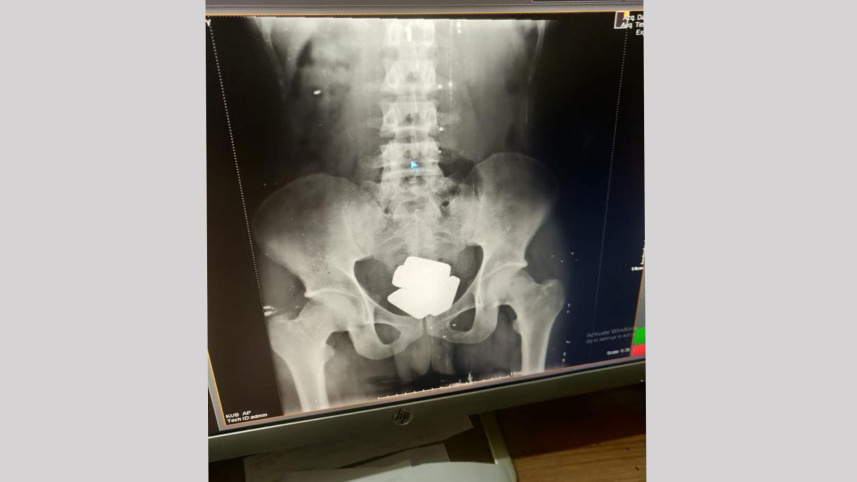

কাস্টমস জানায়, প্রথমে ওই যাত্রীর শরীর তল্লাশি করে ২৩টি স্বর্ণের বার উদ্ধার করা হয়। ধারণা করা হচ্ছিল, তার পেটের ভেতরে (রেক্টামে) আরও স্বর্ণ থাকতে পারে।

শুল্ক গোয়েন্দা ও তদন্ত অধিদপ্তরের চট্টগ্রাম কার্যালয়ের যুগ্ম পরিচালক সাইফুর রহমান তথ্যের সত্যতা নিশ্চিত করে দ্য ডেইলি স্টারকে বলেন, 'স্থানীয় একটি হাসপাতালে নিয়ে চিকিৎসকের পরামর্শে ওই যাত্রীর পেট থেকে আরও ৯টি স্বর্ণের বার উদ্ধার করা হয়।'